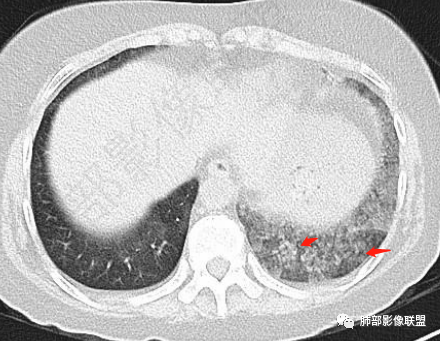

小兜:女,57岁,间断咳嗽1月,咳白色粘痰。CT示左肺下叶实变影,周围可见大片磨玻璃密度影,右肺亦见少量斑片状磨玻璃密度影。考虑恶性可能,左肺下叶粘液腺癌伴播散。

宇宙:两肺多发磨玻璃影,边缘模糊,左肺为著,左肺下叶伴实变,增强实变不均匀强化,其内支气管有阻塞、扩张,考虑粘液腺癌。

放射线:左肺下叶实变及双肺磨玻璃影,左下肺病灶周围磨玻璃影,有重力作用,呈叠瓦片状,增强可见血管造影征,考虑左肺下叶粘液腺癌伴双肺播散。

谢加平:中年女性,慢性干咳史,少量白色粘液痰,左肺下混合密度影,实性密度比胸壁软组织低,周围见大片磨玻璃密度,边缘模糊,叠瓦征分布,实边区内血管束边缘模糊(需重建血管束确认分支有无消失),余肺叶散在分布磨玻璃病灶(气道种植),抗炎治疗无效,左肺下叶符合肺炎型粘液腺Ca并双肺叶气道飘散转移!

患者,女性,57岁。咳嗽1月、咳痰4天,亚急性病史,抗炎效果不佳,体温不高,痰为白色黏痰,白细胞稍高,主病灶在左下叶,实变+GGO,其余肺也有GGO,伴随有结节。

本例病例老年女性,慢性病程,抗炎效果不佳。CT示左肺下叶实变影,周围可见大片磨玻璃密度影,密度不均。右肺亦见少量斑片状磨玻璃密度影。增强可见血管造影征,结合南大分析,排除真菌,结核等,答案就呼之欲出了。